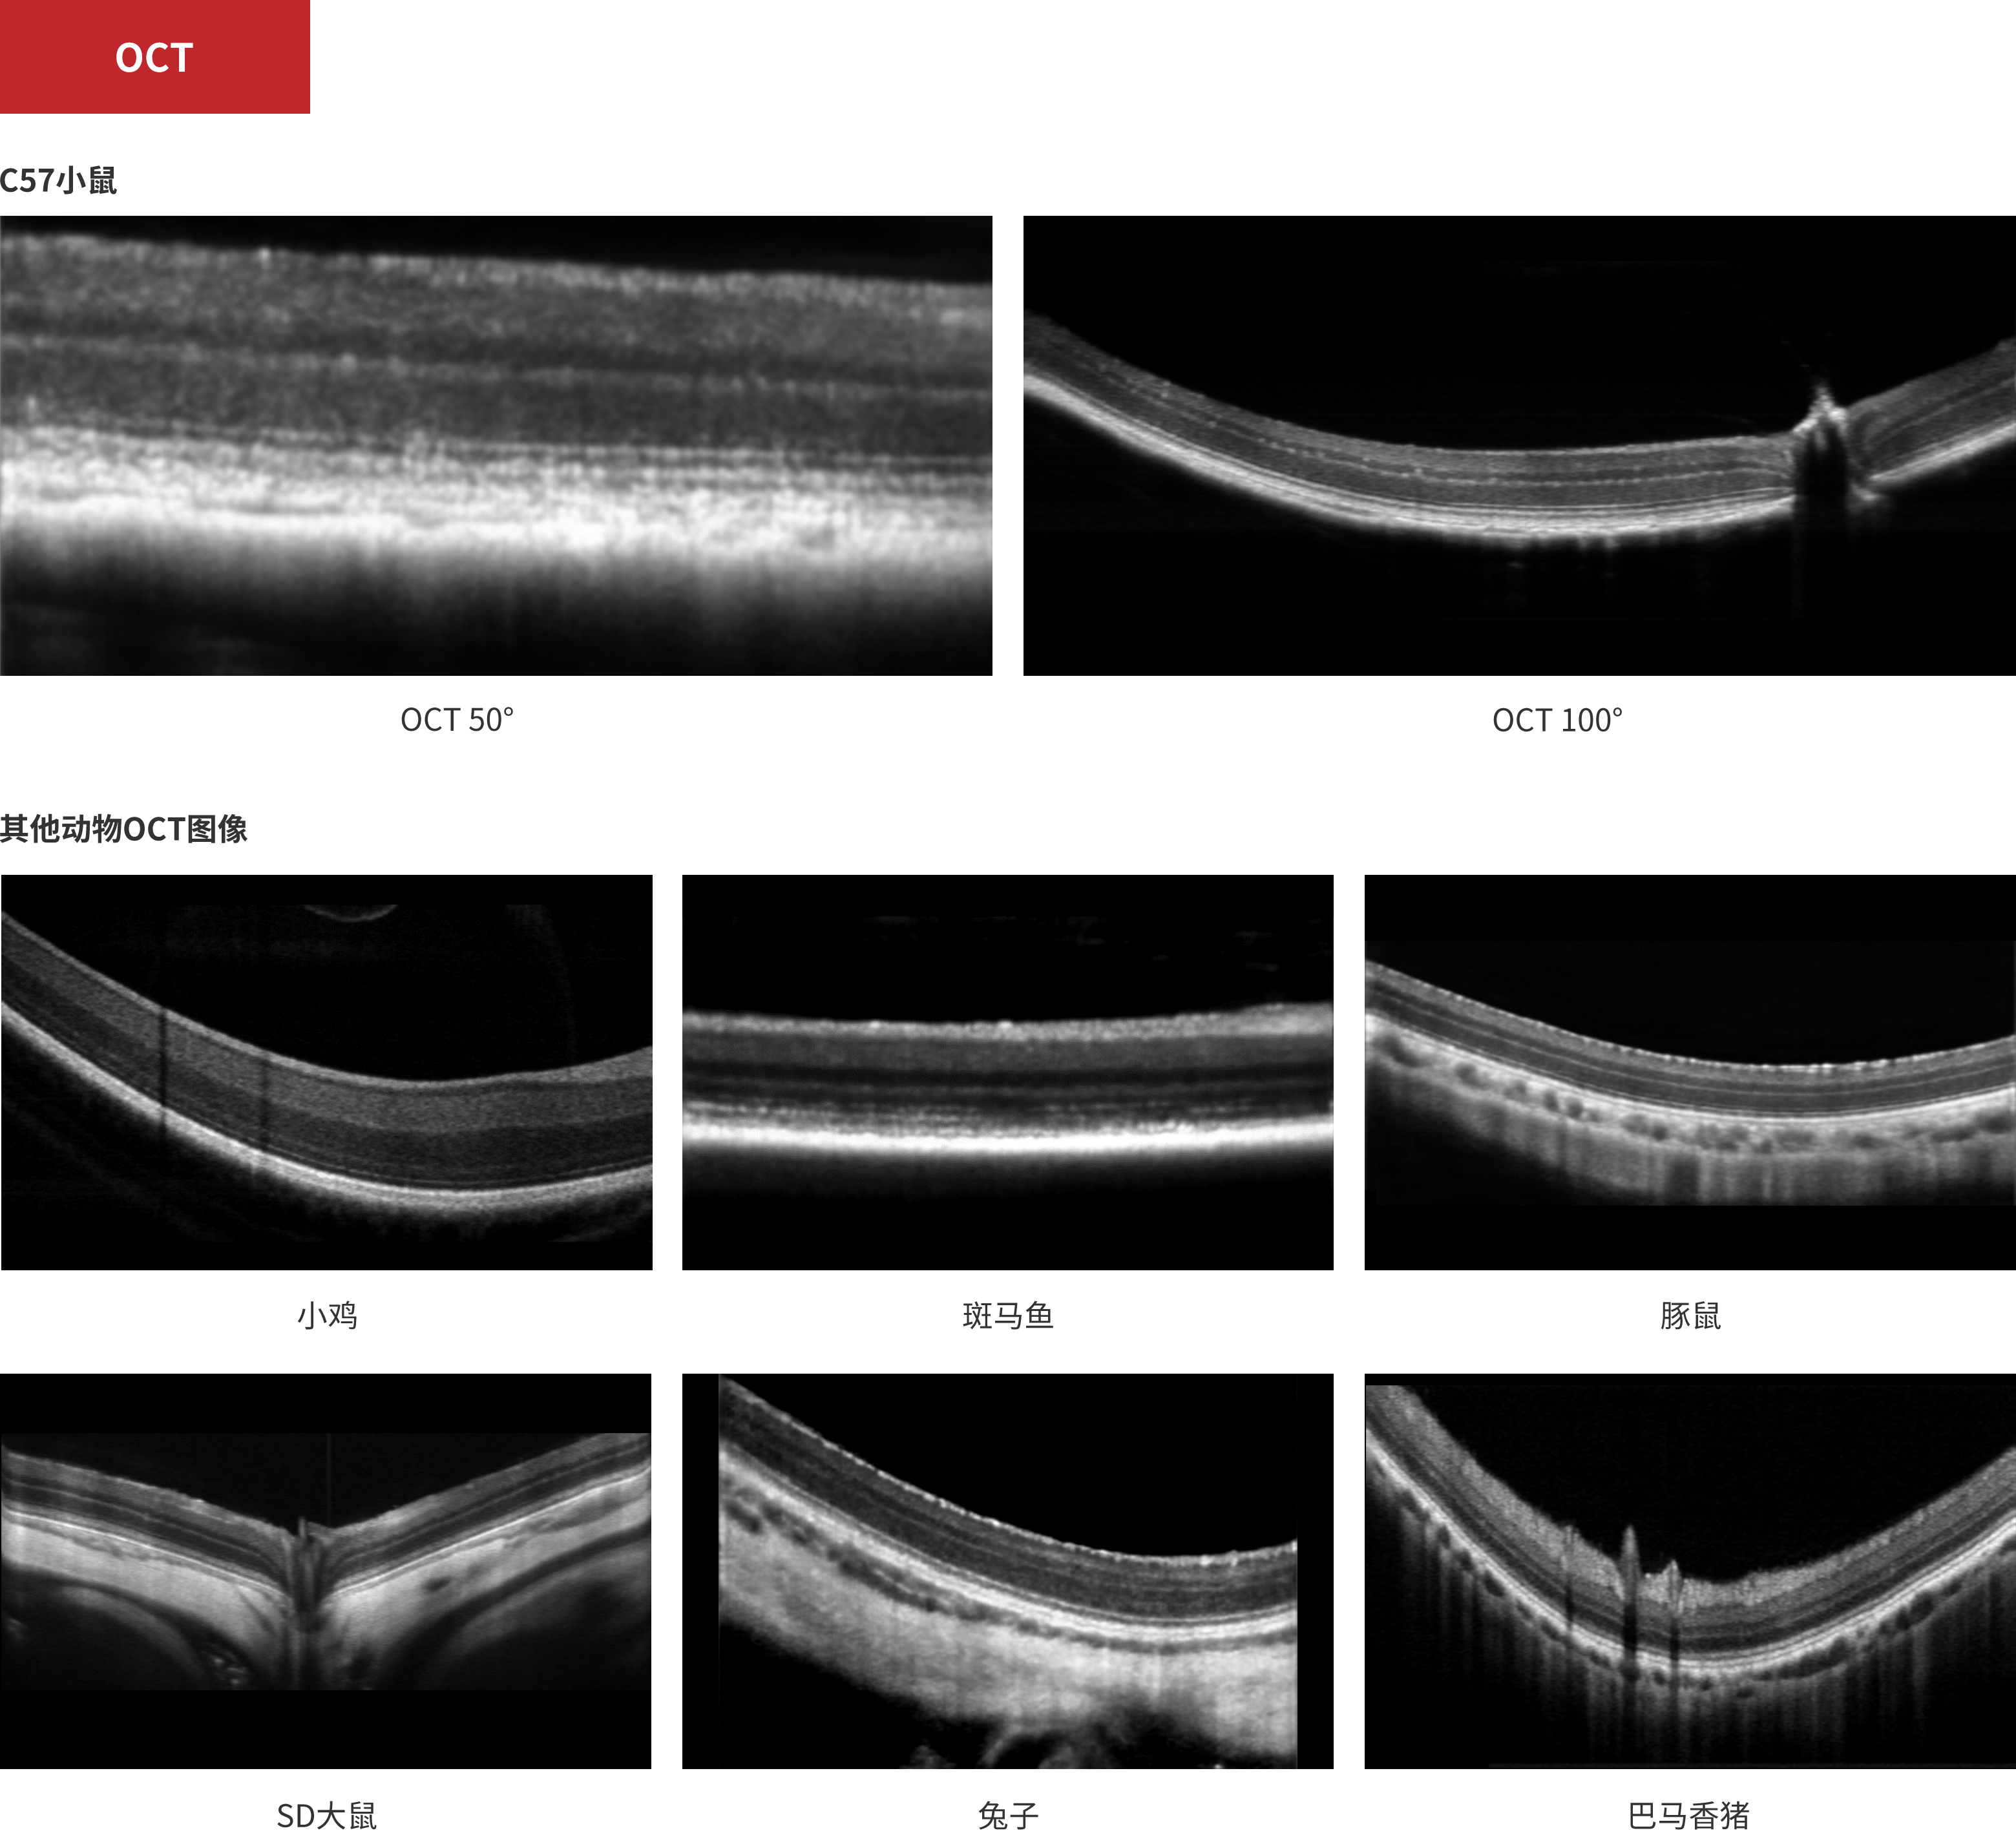

科研

荧光图像